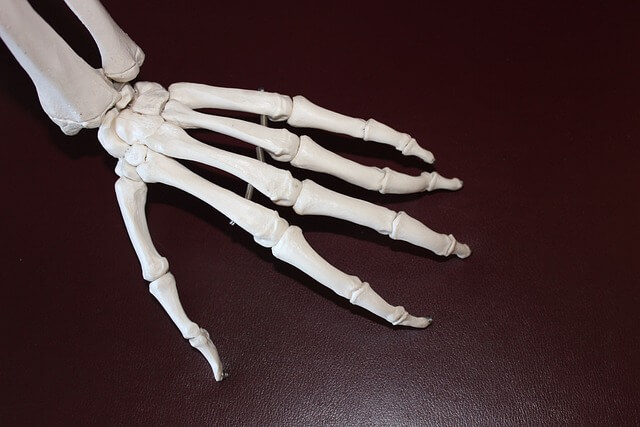

콘드로이친은 주로 다음과 같은 성분으로 구성되어 있습니다.

- 콘드로이틴 황산 : 연골의 주요 성분으로, 관절의 윤활과 충격 흡수 기능을 담당합니다.

- 글루코사민 : 종종 콘드로이친과 함께 사용되며, 연골의 재생을 촉진하는 데 도움을 줍니다.

- 비타민 C : 콜라겐 합성을 도와 연골 건강을 지원합니다.